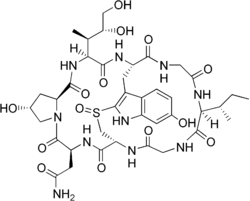

The species is now known to contain two main groups of toxins, both multicyclic (ring-shaped) peptides, spread throughout the mushroom tissue: the amatoxins and the phallotoxins. Another toxin is phallolysin, which has shown some hemolytic (red blood cell–destroying) activity in vitro. An unrelated compound, antamanide, has also been isolated.

Amatoxins consist of at least eight compounds with a similar structure, that of eight amino-acid rings; they were isolated in 1941 by Heinrich O. Wieland and Rudolf Hallermayer of the University of Munich.[32] Of the amatoxins, α-amanitin is the chief component and along with β-amanitin is likely responsible for the toxic effects.[57][58] Their major toxic mechanism is the inhibition of RNA polymerase II, a vital enzyme in the synthesis of messenger RNA (mRNA), microRNA, and small nuclear RNA (snRNA). Without mRNA, essential protein synthesis and hence cell metabolism grind to a halt and the cell dies.[59] The liver is the principal organ affected, as it is the organ which is first encountered after absorption in the gastrointestinal tract, though other organs, especially the kidneys, are susceptible.[60] The RNA polymerase of Amanita phalloides is insensitive to the effects of amatoxins, so the mushroom does not poison itself.[61]

The phallotoxins consist of at least seven compounds, all of which have seven similar peptide rings. Phalloidin was isolated in 1937 by Feodor Lynen, Heinrich Wieland's student and son-in-law, and Ulrich Wieland of the University of Munich. Though phallotoxins are highly toxic to liver cells,[62] they have since been found to add little to the death cap's toxicity, as they are not absorbed through the gut.[59] Furthermore, phalloidin is also found in the edible (and sought-after) Blusher (Amanita rubescens).[32] Another group of minor active peptides are the virotoxins, which consist of six similar monocyclic heptapeptides.[63] Like the phallotoxins, they do not induce any acute toxicity after ingestion in humans.[59]